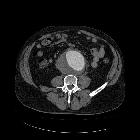

CT

The definitive diagnostic test is contrast-enhanced CT scanning or MRI. Both CT and MRI typically show a periaortic soft tissue mass as a rind of abnormal tissue around the aorta, with a varying extent of spread.

- in IAAA the aorta is aneurysmal

- in isolated periaortitis, the aorta is not aneurysmal and surrounded by a mantle of soft-tissue density

- in IRF, there is usually entrapment of one or both ureters

- fibrosis often manifests as a paraspinal, well-demarcated but irregular retroperitoneal mass, isodense to surrounding muscle

- with CE-CT the periaortic mass usually shows varying degree of enhancement; the degree of enhancement correlates with the activity of the fibrotic process

- in acute stages, avid enhancement is seen, with an increase of 20-60HU

- in chronic disease, little or no enhancement may be seen